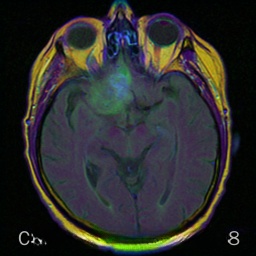

2、Brats2018多模态脑部数据集

Brats 数据集(Brain Tumor Segmentation Benchmark)是专门用于脑肿瘤分割任务的重要医学影像基准数据集。该数据集由来自多个不同医疗机构提供的多模态 MRI 扫描图像构成,并旨在促进脑肿瘤分割算法的研究与性能评估。该集合涵盖了四种不同的 MRI 模式:T1、T2、T1cecho 以及 Flair 成像技术下的高质量参考标注

数据处理方式为:采用分层切片法将3D图像数据经过分层切片处理得到二维图片,并接着使用分割标签来创建检测框。

经过良好处理后的VOC格式的数据集中,在图像中的单个模态中总计共有15,424张图像,其中类型标签主要集中在病灶区域,并且包含来自四个不同模态的VOC数据